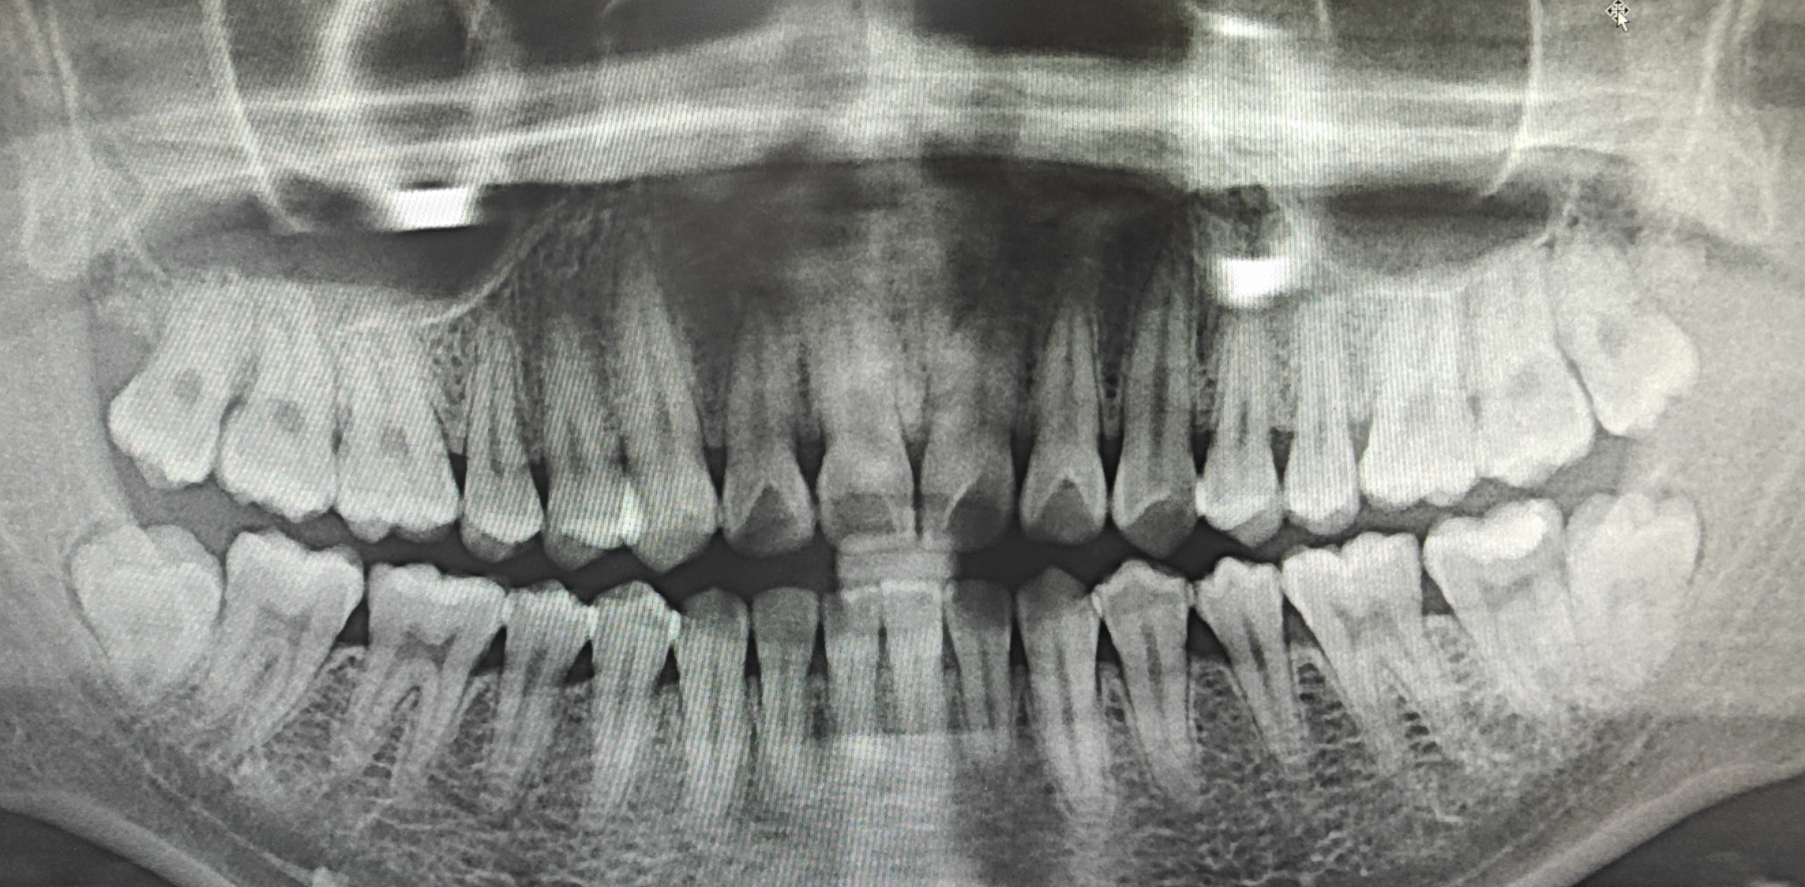

全景片(看全口牙齿排列、颌骨情况):辐射量稍高,但单次也只有 9-24μSv。举个更贴近的例子:香蕉本身含有天然放射性物质钾 - 40,吃 1 根香蕉大概会摄入 1μSv 的辐射。拍一次全景片的辐射,相当于吃 10-24 根香蕉的量,是不是听起来没那么吓人了?

CBCT(锥形束 CT,看种植牙、复杂阻生智齿等):辐射量相对更高,但也分 “小视野” 和 “大视野”。小视野 CBCT(只拍局部)大约 84μSv,相当于做一次胸部 X 光(约 100μSv);大视野 CBCT(拍全颌骨)大约 212μSv,相当于 10 天的自然本底辐射(我们每天呼吸、晒太阳,自然环境中的辐射大约 20μSv / 天)。

只有 “必须用 X 线辅助诊断” 时才会开检查。比如蛀牙太深到牙神经、智齿位置复杂可能伤邻牙、种植牙需要精确测量骨量 —— 这些情况,X 线能帮医生看得更清楚,避免误诊漏诊。